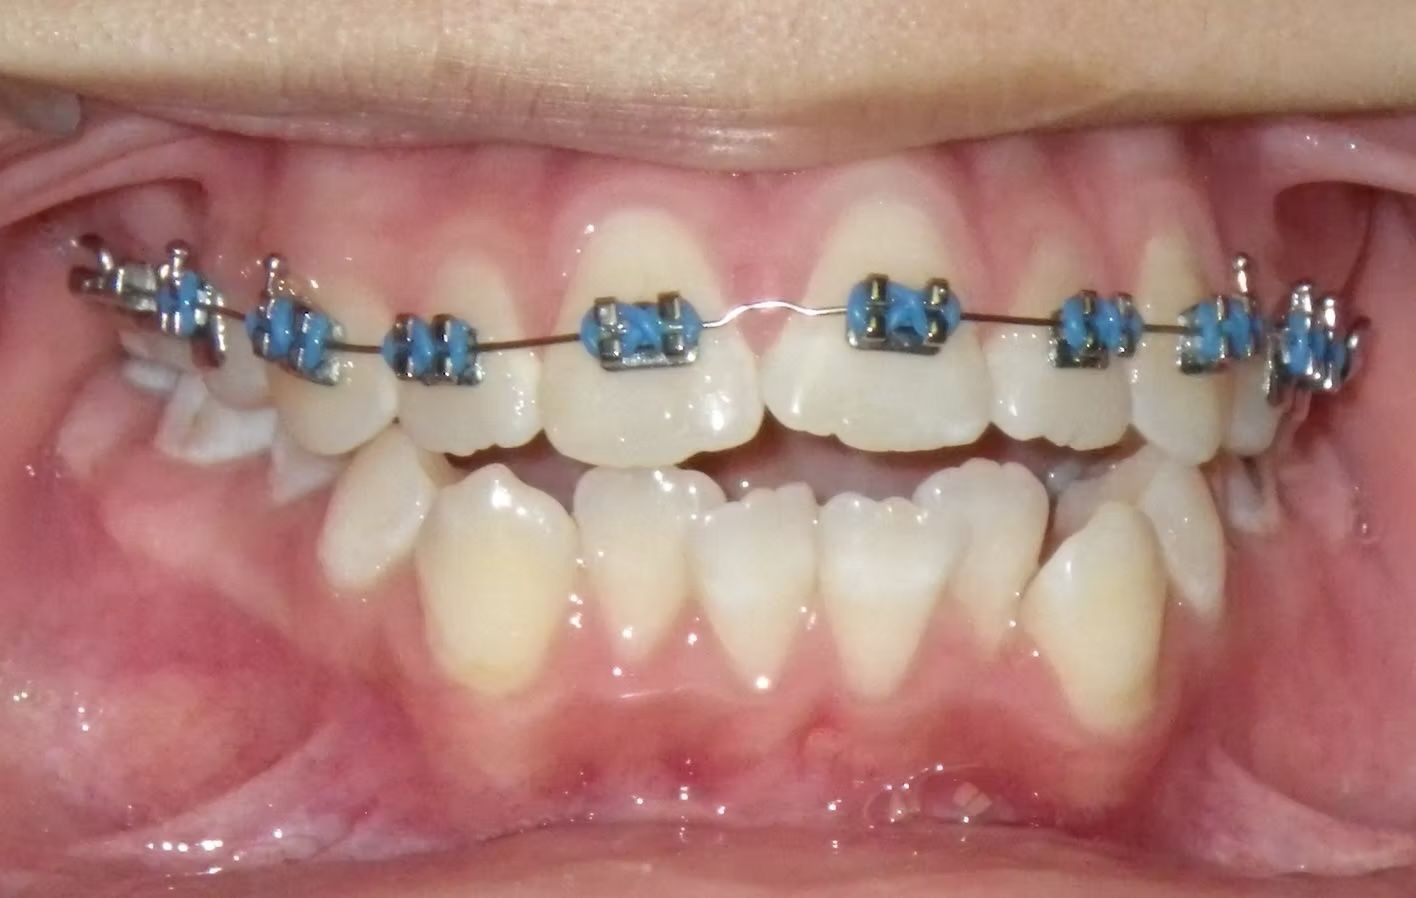

Johntavious

Johntavious didn't like that one of his lower teeth was set behind the rest. He went to many orthodontists who told him to extract the tooth or multiple teeth to correct the alignment. Johntavious and his parents didn't want to go that route and wanted to try to align the teeth without the extraction. Dr. Bret was able to successfully straighten the upper and lower teeth - fit the tooth that was back into the dental arch and make Johntavious and his parents really happy.